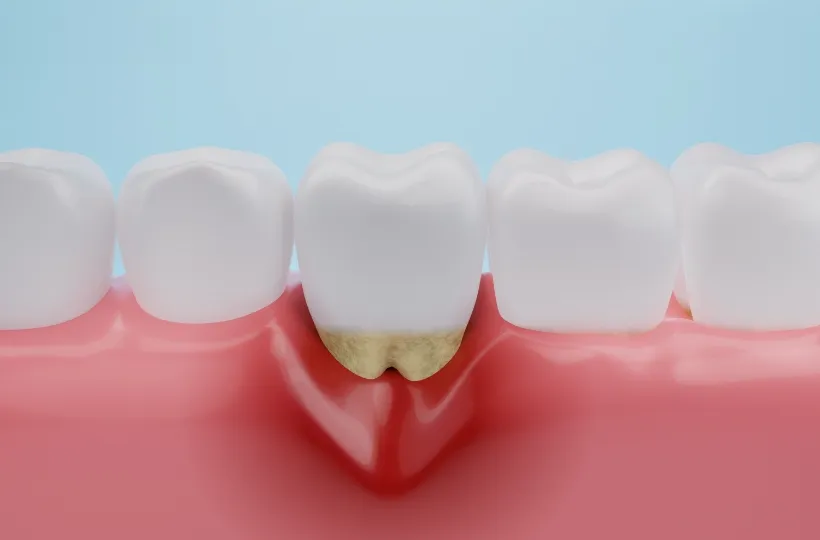

歯周病治療

歯磨きが不充分だと歯肉が炎症を起こし、放置していると歯が抜けてしまいます。医院でのプロによるクリーニングと日々の歯磨きで清潔な状態を保ち、健康を維持します。